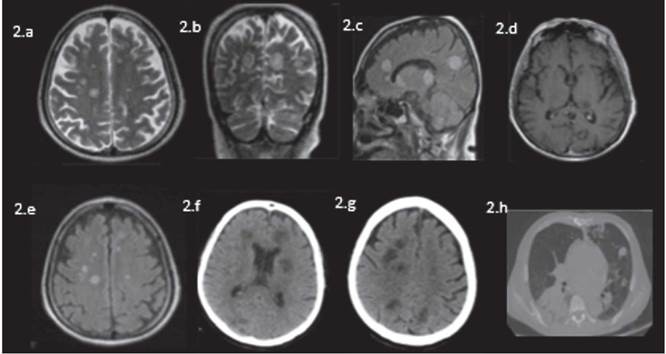

Imágenes de resonancia magnética nuclear en equipo de 1,5 UT con cortes axiales en eco axial en Dwi (e), ADCwi (f), T2 (g), Sag T1 (h) identificando múltiples lesiones focales distribuidas indistintamente en los hemisferios cerebrales de aspecto inflamatorios de alta intensidad de señal en T2 y flair, baja señal en T1 con restricción de la difusión.

Figura 1: Imágenes de resonancia magnética nuclear en equipo de 1,5 UT con cortes axiales en eco axial en Dwi (e), ADCwi (f), T2 (g), Sag T1 (h) identificando múltiples lesiones focales distribuidas indistintamente en los hemisferios cerebrales de aspecto inflamatorios de alta intensidad de señal en T2 y flair, baja señal en T1 con restricción de la difusión.

Los estudios de RM cerebral del caso en estudio mostraron innumerables lesiones redondeadas de baja señal en secuencias potenciadas en T1 y alta señal en secuencias potenciadas en T2 y FLAIR, que comprometían tanto la fosa posterior como la región supratentorial, de predominio subcortical y en sustancia blanca, algunas de ellas también en núcleos de la base de ambos hemisferios y en la región talámica izquierda con diámetros entre 5 y 19 mm, y solo algunas de ellas presentaron un sutil realce en anillo sin edema perilesional, con alta señal en las secuencias de difusión y baja señal en los mapas de ADC.